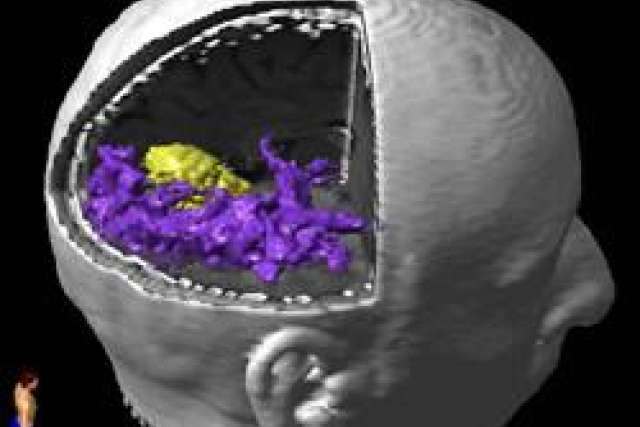

Dr. Linda Liau met Robert and decided that surgical resection of the mass would be the most appropriate treatment choice given his symptoms and increasing size of the lesion. As the mass was located in an area that would result in obvious neurologic deficits if disrupted (visual cortex), preoperative functional MRI (fMRI) and diffusion tensor imaging (DTI) data was obtained in order to help map out the relation of the mass to critical visual fibers for navigation in the OR. This helps the surgeon intraoperatively by guiding resection and avoiding areas critical for neurologic function. [Purple = visual fibers; yellow = tumor].

Diffusion tensor imaging 3D view: